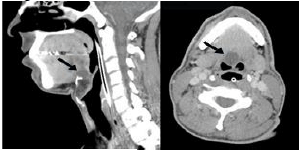

Analise as imagens de tomografia computadorizada a abaixo e assinale a alternativa que melhor representa o diagnóstico.

Provas